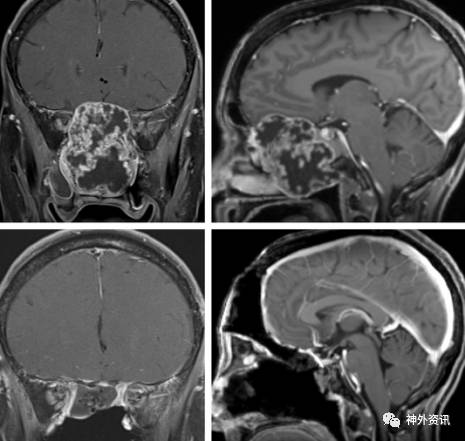

图1. 广泛侵犯鼻腔的前颅底软骨肉瘤(上图)。本病例用于阐明双额入路的适用对象。由于肿瘤侵犯鼻中隔导致其不能用于颅底重建,故经鼻入路在本病例并不适用。下面的两图展示的是肿瘤全切后的影像学表现。